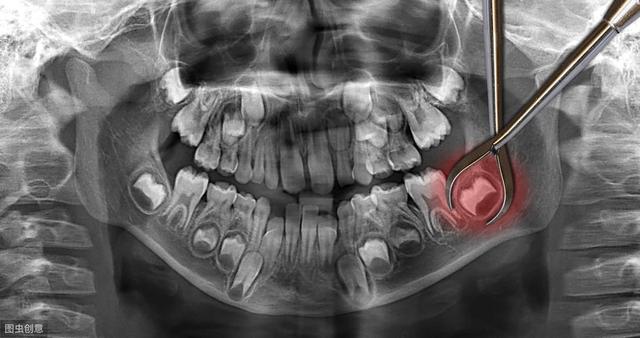

这种情况下,尽早拔掉阻生智齿就是免除后顾之忧最好的选择。甚至我们在条件允许的情况下趁早下手,可以提前拔除智齿的牙胚,不让它有萌出和干扰其他牙齿的机会。现在检查智齿都会拍X全景片,片里可以清楚地看到有没有智齿牙胚,如果没有太大风险的(比如牙胚位于下颌神经管内),我们都可以在智齿萌出之前,选择合适的时机进行开窗拔除牙胚,不让它有作乱的机会。